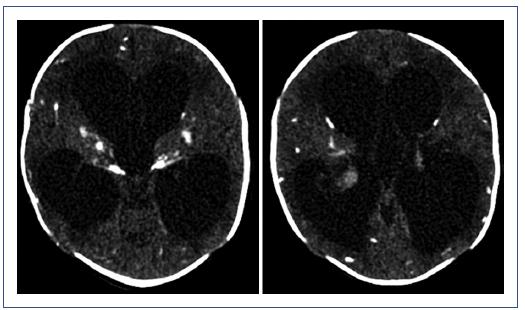

Con base en estos datos se sospechó TC, por lo cual se realizaron pruebas para T. gondii con los siguientes resultados: IgG 164 U/ml, IgM 0.8 U/ml (positivo > 1.1), IgA 2.8 U/ml (positivo > 11) y test de avidez IgG 0.156 (bajo). Otros datos del TORCH, como la carga viral para citomegalovirus, rubeola y virus de la inmunodeficiencia humana, fueron negativos. No se realizaron serologías para T. gondii durante la gestación. A pesar de las serologías negativas, se pudo observar un cuadro clínico sugestivo de TC en la tomografía computarizada de cráneo, que mostró calcificaciones difusas (Fig. 3). Ante esta evidencia, se tomó una nueva muestra de LCR para estudio por reacción en cadena de la polimerasa (PCR) y serología. Los resultados de ambos estudios fueron positivos, por lo que se confirmó la infección congénita: IgM en LCR para T. gondii de 1.1 (ensayo inmunoenzimático positivo).

Figura 3 Ectasia ventricular supratentorial con posible zona de estrechez del acueducto de Silvio. Se aprecian extensas áreas de hipodensidad de la sustancia blanca en los lóbulos frontales y parietales, las regiones periventriculares, la unión troncoencefálica y los lóbulos temporales. También se observan áreas de posible malacia de la sustancia blanca periventricular y adyacente a las regiones ganglio basales bilaterales, especialmente del lado izquierdo, aunado a extensas áreas de encefalomalacia temporal bilateral, relativamente simétricas. Asimismo, se observan múltiples macrocalcificaciones y calcificaciones lineales que comprometen los territorios fronto-parieto-temporo-occipital bilaterales y la unión troncoencefálica, los núcleos grises, los plexos coroideos y los lóbulos temporales. Borramiento parcial de los surcos cerebrales de manera generalizada.